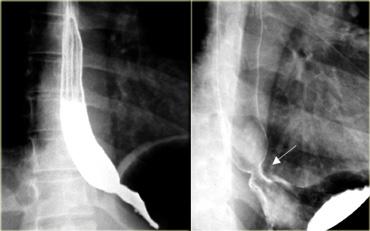

Bên trái là hình ảnh của một nam giới 52 tuổi không có triệu chứng.

Hình chiếu thẳng (AP) và hình chiếu nghiêng cho thấy màng mỏng, ngắn (mũi tên) với mức độ nhô vào lòng ống tối thiểu.

Bên trái là hình ảnh của một phụ nữ 42 tuổi bị khó nuốt do màng thực quản.

Lòng ống bị hẹp > 50%